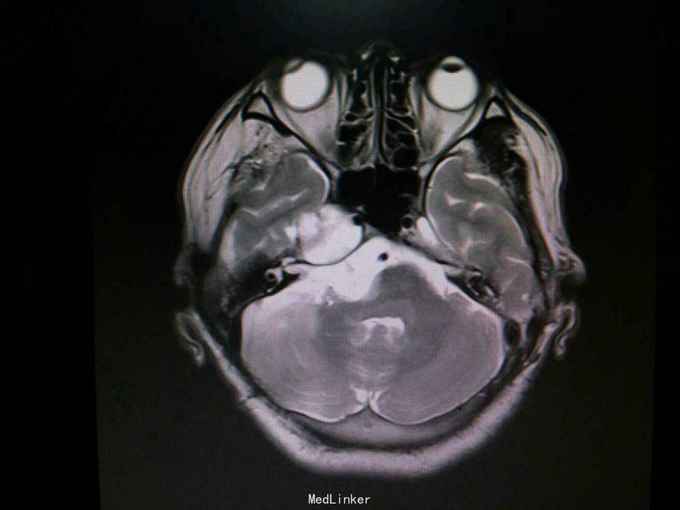

查体:生命体征平稳。神经系统检查:右侧眼睑下垂,左侧眼睑无下垂。肌力 右侧肢体肌力5-级,左侧肢体肌力正常。肌张力: 右上肢肌张力正常,右下肢肌张力正常;左上肢肌张力正常,左下肢肌张力正常。肌营养检查:四肢肌肉无萎缩。共济与平衡检查:正常。外院颅脑CT示右侧桥脑小脑角团片囊性低密度区,性质待定,蝶窦右后方局部骨质缺损代之稍低密度软组织肿块,考虑原肿瘤复发,颅骨呈术后改变,颅脑CT增强示颅内占位性病变(表皮样囊肿?)。入院后行颅脑MRI检查提示: 右侧颞骨岩尖-脚间池-右侧环池-右侧桥小脑角池见片状异常信号影,边界清,形态不规则,呈匍匐状分布,冠状位范围约47mm×29mm。相应右侧颞、脑干明显受压,脑干向左移位。第三脑室略向左移位。右侧额骨、颞骨骨皮质欠连续,呈术后改变。 考虑右侧颞骨岩尖-脚间池-右侧环池-右侧桥小脑角池表皮样囊肿。 右侧颅骨呈术后改变。